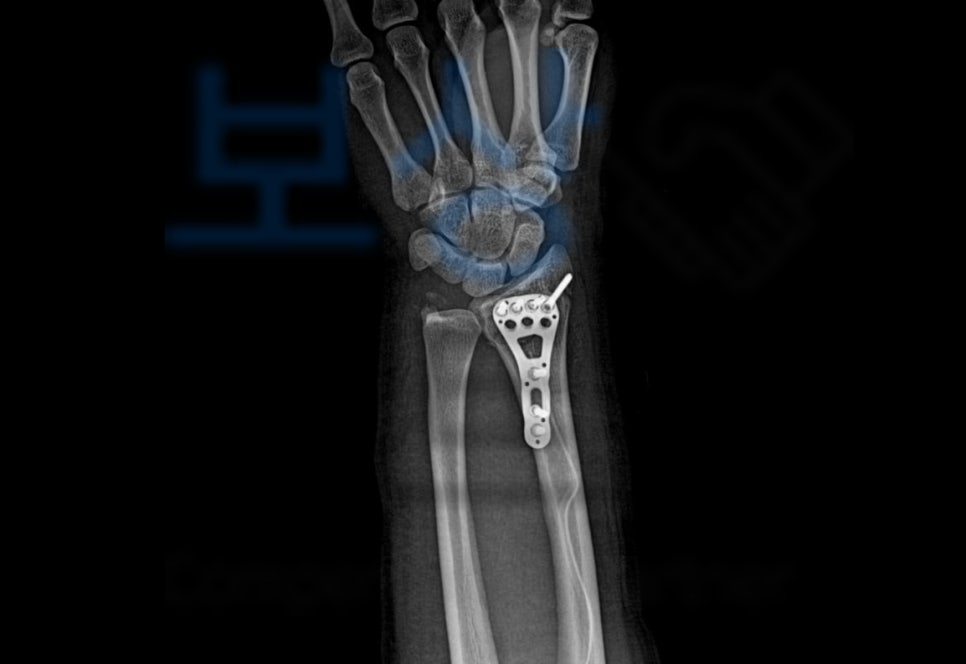

이 사고로 손@@님은 응급실에 내원하셨고

요골 하단의 골절, 즉 손목 골절을 진단받아 금속 고정 후 석고기브스 치료를 받게 되었습니다. 먼저 합의금은 구성 요소는